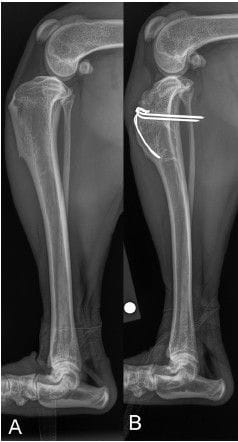

Radiograph of a 1-year-old female mixed breed dog (Case 14).

(A) Normal stifle. (B) Tibial tuberosity avulsion fracture stifle treated

surgically with pin and tension band (group TB).